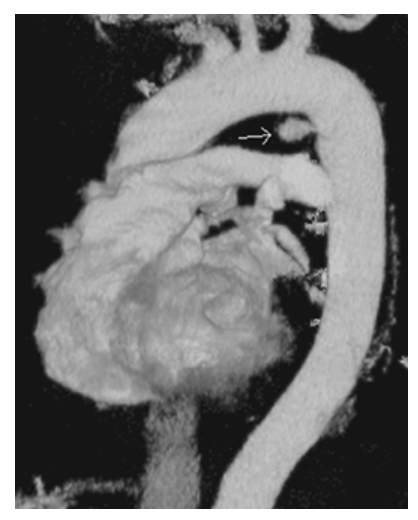

Aortic Tear. CTA volume rendered (VR) in a different patient, shows a posttraumatic pseudoaneurysm (arrow).